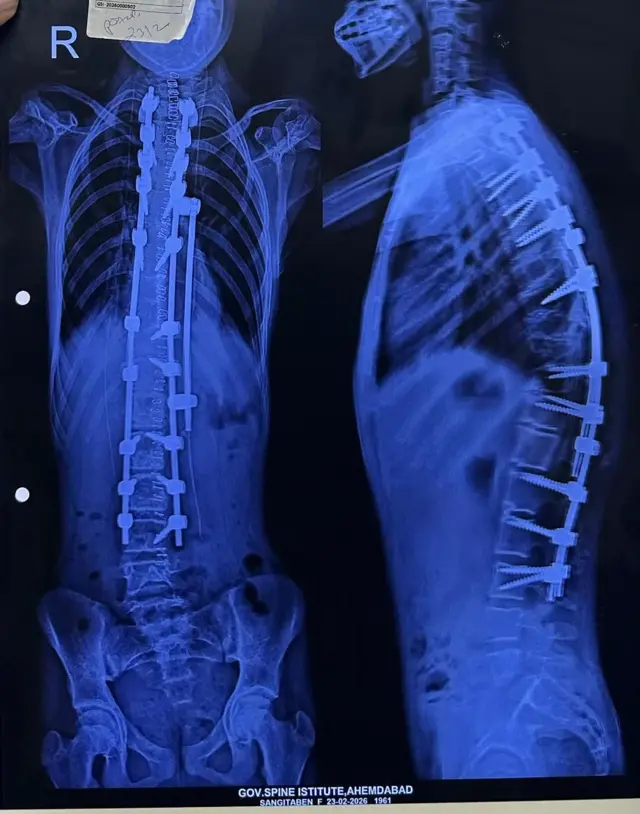

આ બીમારીને તબીબી ભાષામાં કાઇફોસિસ કે સ્કોલિયોસિસ તરીકે ઓળખવામાં આવે છે. માત્ર વિરમભાઈની દીકરી જ નહીં, પરંતુ આ સમસ્યા ધરાવતા સાત બાળકોની 16 ફેબ્રુઆરીના રોજ સર્જરી કરવામાં આવી હતી.

અમદાવાદની સિવિલ હૉસ્પિટલ પરિસરમાં આવેલી ગવર્નમેન્ટ સ્પાઇન ઇન્સ્ટિટ્યૂટ ખાતે બાળકોમાં જોવા મળતી કરોડરજ્જુને લગતી કાઇફોસિસ અને સ્કોલિયોસિસ જેવી ગંભીર બીમારી ધરાવતાં સાત બાળકોની સફળ સર્જરી કરવામાં આવી હતી.

બાળકોમાં જન્મજાત કે નાની ઉંમરે કરોડરજ્જુ વાંકી વળી જવી અથવા કરોડનું હાડકું બહાર દેખાવવા લાગવું જેવાં લક્ષણો જોવાં મળે છે. આ પ્રકારના કિસ્સામાં સમયસર સર્જરી કરીને બાળકોને કાયમી ખોડખાંપણમાંથી મુક્તિ અપાવી શકાય છે.

"જો બાળકની કરોડરજ્જુનો ઉપરનો ભાગ 'D' આકારમાં વાંકી વળતો હોય તો તેને કાઇફોસિસ કહેવાય છે. જ્યારે કરોડરજ્જુનો નીચેનો ભાગ ત્રાંસો થતો હોય કે 'S' આકારમાં વળતો હોય તો તેને સ્કોલિયોસિસ કહેવાય છે. કેટલાંક બાળકોમાં આ બંને સમસ્યા એકસાથે જોવા મળે છે, જેને 'કાઇફોસ્કોલિયોસિસ' કહેવાય છે."